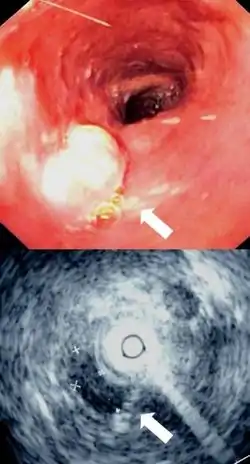

Cancer

There are two main types of cancer of the esophagus. Squamous cell carcinoma is a carcinoma that can occur in the squamous cells lining the esophagus. This type is much more common in China and Iran. The other main type is an adenocarcinoma that occurs in the glands or columnar tissue of the esophagus. This is most common in developed countries in those with Barrett's esophagus, and occurs in the cuboidal cells.[5]

In its early stages, esophageal cancer may not have any symptoms at all. When severe, esophageal cancer may eventually cause obstruction of the esophagus, making swallowing of any solid foods very difficult and causing weight loss. The progress of the cancer is staged using a system that measures how far into the esophageal wall the cancer has invaded, how many lymph nodes are affected, and whether there are any metastases in different parts of the body. Esophageal cancer is often managed with radiotherapy, chemotherapy, and may also be managed by partial surgical removal of the esophagus. Inserting a stent into the esophagus, or inserting a nasogastric tube, may also be used to ensure that a person is able to digest enough food and water. As of 2014, the prognosis for esophageal cancer is still poor, so palliative therapy may also be a focus of treatment.[5]

Imaging

An X-ray of swallowed barium may be used to reveal the size and shape of the esophagus, and the presence of any masses. The esophagus may also be imaged using a flexible camera inserted into the esophagus, in a procedure called an endoscopy. If an endoscopy is used on the stomach, the camera will also have to pass through the esophagus. During an endoscopy, a biopsy may be taken. If cancer of the esophagus is being investigated, other methods, including a CT scan, may also be used.[5]